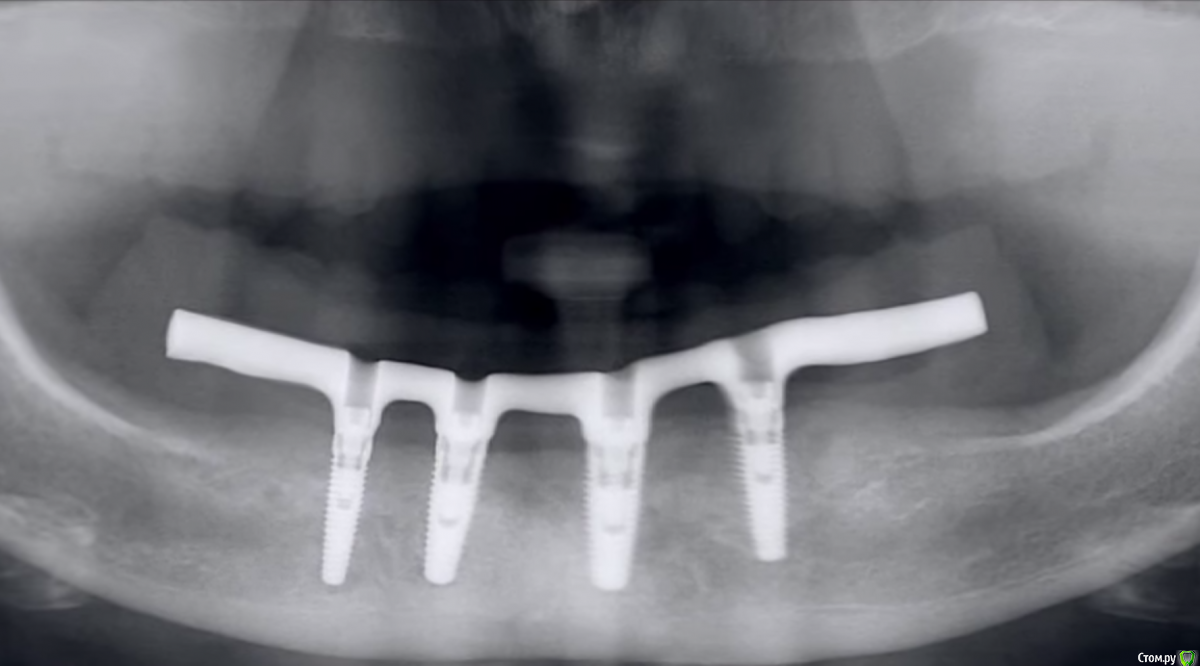

Evikrol Опубликовано 13 апреля, 2015 Поделиться Опубликовано 13 апреля, 2015 Выше приведена времянка (надеюсь), так что есть шанс, что мы не так поняли.А вот тут готовая работа. Тоже есть вопросы. Называют это "все на четырех". Снимок экрана 2015-04-12 в 22.03.47А вообще что это на последней фото? Несъемный-съемный протез, это постоянная работа не временная? А гигиена как? Ссылка на комментарий

Doc Опубликовано 13 апреля, 2015 Поделиться Опубликовано 13 апреля, 2015 А вообще что это на последней фото? Несъемный-съемный протез, это постоянная работа не временная? А гигиена как?написали, что это условно-несъемный протез по системе "все на четырех". Подробностей не знаю, не видел. Мне просто прислали это с вопросом что общего это имеет с концепцией? На мой взгляд ничего. Ссылка на комментарий

doctore Опубликовано 13 апреля, 2015 Поделиться Опубликовано 13 апреля, 2015 Я помогу с ответами пожалуй )) Первое оптг -работа Макса Копылова - наверху будет доставлено еще 2 винта в дистальных отделах. Сейчас стоит временная конструкция.Вторая оптг- моя работы. Условно сьемный протез.Какие вопросы к гигиене? 1 Ссылка на комментарий

Evikrol Опубликовано 13 апреля, 2015 Поделиться Опубликовано 13 апреля, 2015 Можно я задам ещё пару вопросов, если вы не против, по поводу данной работы. Значит пациент не может снять сам нижний протез? Как правильно выполнять промывное пространство, нужно ли оно там, как правильно должен выглядеть такого рода протез? Ссылка на комментарий

Doc Опубликовано 14 апреля, 2015 Поделиться Опубликовано 14 апреля, 2015 Doc, расскажите пожалуйста, почему эта работа или та что ниже не соответствует концепции "все на 4х?" И, если есть такая возможность, объясните пожалуйста, чем ещё концепция "all in 4" отличается от просто четырех имплантов на одной беззубой челюсти?Потому что концепция совсем другая и подразумевает установку двух дистальных имплантатов под углом с использованием специальных угловых абатментов. Я где-то на форуме выкладывал уже подобные работы, поищите, там все ясно и понятно. Что касается верхней работы, то как благополучно выяснилось, там планируется добавить еще два имплантата и тот факт, что это работа Максима Копылова уже гарантирует, что она будет сделана по всем правилам. Максим не тот человек, чтобы делать всякую ерунду. Я не зря предположил, что мы чего-то про эту работу не знаем. Ну а нижняя работа, как я понял, уже окончательная и там доктор рассчитывает на верхний съемный протез и что нагрузка будет минимальная, потому хватит и четырех имплантатов. Скорее всего так и есть, и при адекватном осторожном использовании эта работа простоит дольше, чем пациент проживет, но это совсем не "все на четырех", т.к. это уже торговая марка и она подразумевает определенный протокол. Ссылка на комментарий

doctore Опубликовано 14 апреля, 2015 Поделиться Опубликовано 14 апреля, 2015 А вот почему Вы это назвали "все на четырех"? Ведь это близко не лежало к нашему товарищу Мало и его концепции. Я как-то в приличном обществе сказал фразу "сделал все на шести", так меня заклевали за использование неправильных определений, а то была просто аналогия-калька. ну,Мало концептуально говорит о соответствующем расположении винтов, как вы правильно заметили и о протоколе. Что не исключает возможности иного подхода в расположении имплантатов , как и в названии . На четырех ? На четырех ))На верхней челюсти действительно полный сьемный протез . И возраст пациента подразумевает достаточный для него срок службы конструкции Ссылка на комментарий

doctore Опубликовано 14 апреля, 2015 Поделиться Опубликовано 14 апреля, 2015 Можно я задам ещё пару вопросов, если вы не против, по поводу данной работы. Значит пациент не может снять сам нижний протез? Как правильно выполнять промывное пространство, нужно ли оно там, как правильно должен выглядеть такого рода протез? Вы правы- сам пациент снять данной работы не может.Отсюда и название - условно сьемный. В клинике мы снимаем его каждый год для гигиены с заменой винтов.Я предпочитаю моделировку промежуточной придесневой части выполнять с формированием овоидов если позволяет форма гребня и обьем мягких тканей. Ссылка на комментарий